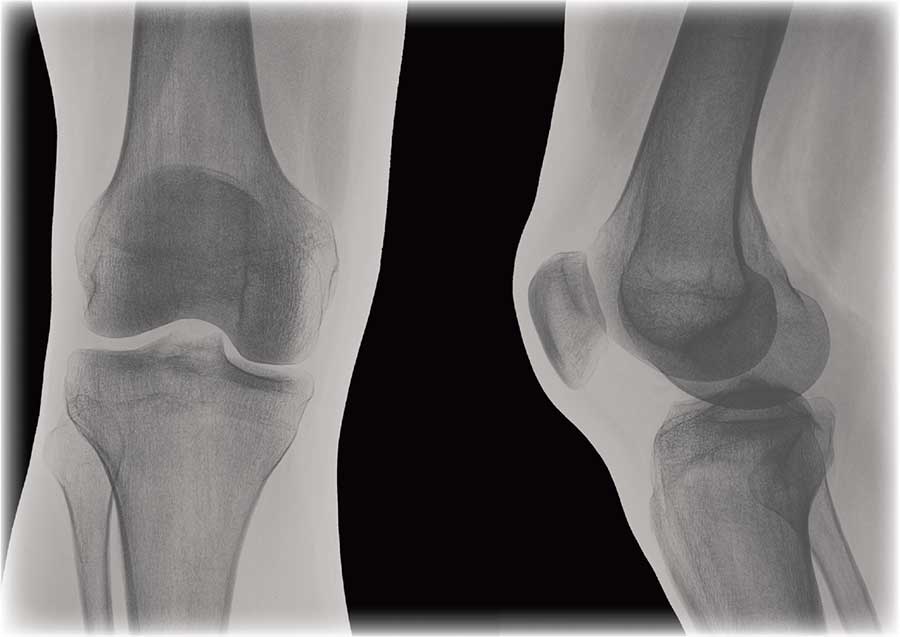

Соединение костей в коленном суставе (вверху – рентген, внизу – модель)

Суставные поверхности костей, образующие сустав, плотно прилегают друг к другу. Они покрыты особым гиалиновым хрящом, чья гладкая поверхность и эластичность облегчают движение в суставе, смягчают испытываемые им толчки и сотрясения.

Суставные поверхности костей окружает суставная капсула – оболочка из соединительной ткани. Обычно она крепится к костям в месте перехода суставной поверхности в надкостницу и прочно с ней срастается. Снаружи капсула укреплена связками, которые располагаются в местах наибольшей нагрузки.

Суставные поверхности и капсула ограничивают собой небольшое герметично закрытое пространство – полость сустава, заполненную малым количеством вязкой синовиальной жидкости, роль которой заключается в уменьшении трения в суставах при движении. Благодаря отрицательному давлению в суставной полости поверхности костей тесно прилегают друг к другу.